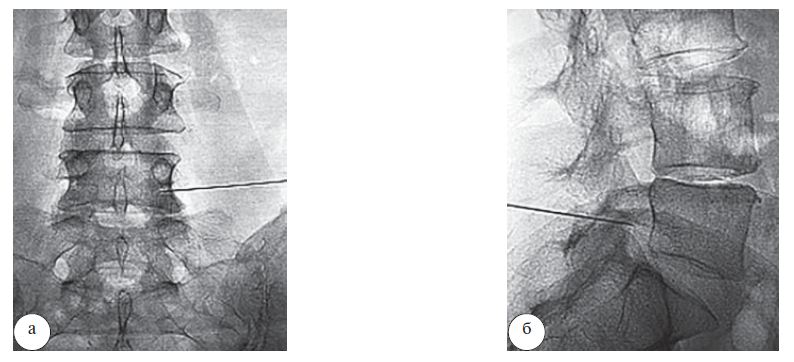

При радиочастотной импульсной модуляции осуществлялся пункционный заднебоковой трансфораминальный доступ [1] к выходящему из межпозвонкового отверстия спинномозговому нерву [5]. Правильное позиционирование электрода подтверждалось сенсорной и моторной стимуляцией. Положительными результатами стимуляции являлись возникновение парестезий и наличие моторных ответов в соответствующих группах мышц. Далее выполнялась модуляция спинномозговых ганглиев при следующих параметрах воздействия: частота импульса – 2 Гц, ширина спектра импульса – 20 мс, максимальное напряжение – 45 В, время воздействия – 240 с (рис. 2).

Рис. 2. Интраоперационная спондилография при радиочастотной импульсной модуляции: а – прямая проекция; б – боковая проекция